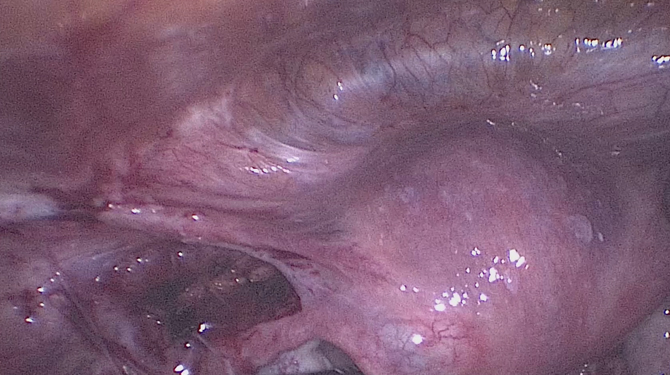

Hysteroscopy

• Operative hysteroscopy is used to correct an abnormal condition that has been detected during a diagnostic hysteroscopy. If an abnormal condition was detected during the diagnostic hysteroscopy, an operative hysteroscopy can often be performed at the same time, avoiding the need for a second surgery. During operative hysteroscopy, small instruments used to correct the condition are inserted through the hysteroscope.